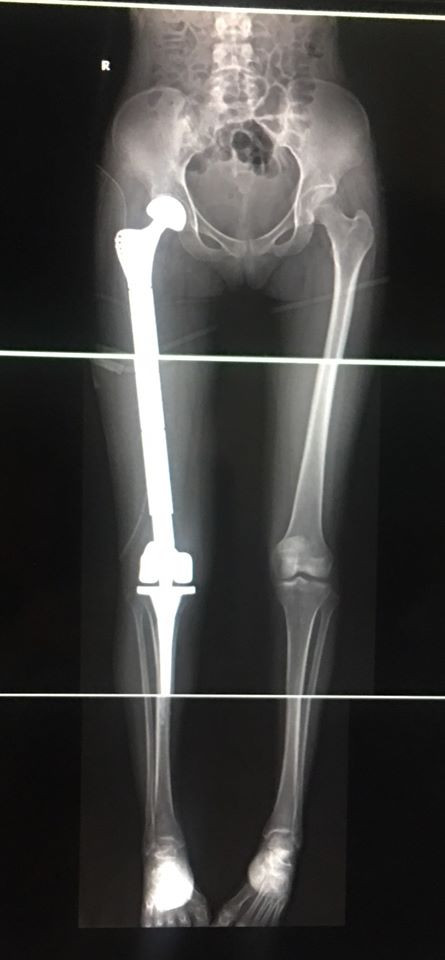

![]() |

| Phim chụp lại sau mổ của bệnh nhân H. Ảnh: Sơn Tùng |

Sau thành công của ca mổ kỳ tích này, PGS.TS. Trần Trung Dũng cho biết: “Ca phẫu thuật đã diễn ra khẩn trương và an toàn, toàn bộ xương ung thư của bệnh nhân H. đã được lấy ra và thay bằng xương đùi Titan. Do mất ít máu trong khi mổ, nên bệnh nhân sẽ sớm hồi phục, giữ được chức năng của chi và có thể vận động bình thường trở lại.”

Ca phẫu thuật diễn ra đầy căng thẳng trong 3 tiếng đồng hồ cuối cùng đã thành công nhờ kinh nghiệm và tay nghề cao của PGS.TS. Trần Trung Dũng. Toàn bộ xương đùi ung thư của cô gái trẻ đã được lấy ra để thay thế bằng xương đùi Titan, đồng thời thay khớp háng và khớp gối toàn phần và khâu phục hồi lại các điểm bám gân cơ.